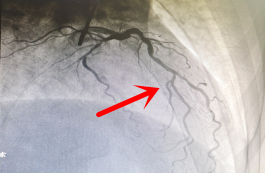

【术前造影】

2022年3月初,60岁的聂叔叔,因“阵发性胸闷胸痛1月,加重3天入院”,住院期间行冠脉造影检查示左前降支主支自开口完全闭塞,TIMI血流0级。经过我科介入团队通力合作,历时2小时成功开通患者前降支闭塞病变。术后胸闷痛症状明显缓解,日前已顺利出院,生活质量较前提高。